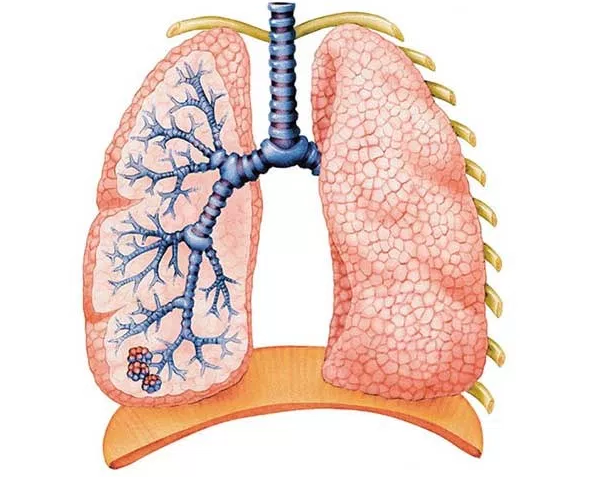

肺癌病人吃什么好?肺癌病人久病后导致体质衰弱,热量和蛋白质消耗较多,营养状态较差,免疫功能低下,不利于患者身体的恢复,因此,肺癌患者不宜过分强调忌口。肿瘤病人的复发与转移,与是否忌口并无关系,只要是想吃就可以吃,吃下去舒服就行。

可通过补充饮食营养和水分来调理。肺癌患者每餐应适当配备富有高热量、高蛋白、高维生素的半流质饮食,如蛋类、牛奶、瘦肉、鸡肉、大米、面食、米粥、鱼类、蔬菜、水果等。绝对戒烟和禁止酗酒,避免进食虾、螃蟹等寒性且容易引起过敏的食物,避免食用辛辣等刺激之物。

肺癌的饮食护理都要多吃新鲜蔬菜和水果,果蔬中含有丰富的维生素C,是抑癌物质,能够阻断癌细胞的生成,另外大蒜也含有抗癌物质。养成良好的生活和饮食习惯。